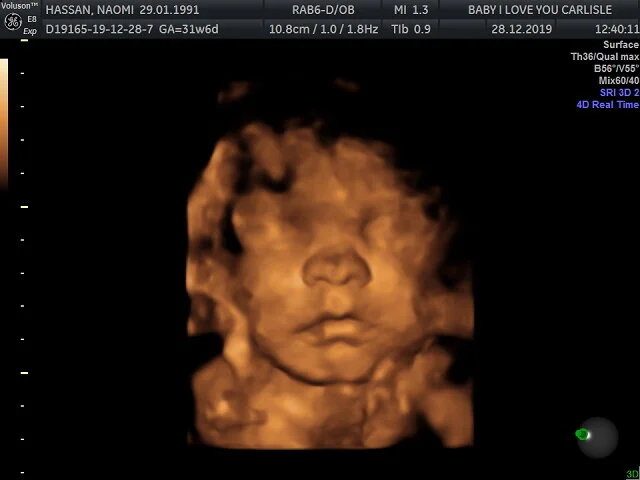

I was 31+6 weeks pregnant with Munchkin when we went for his 4D scan.

We had another difficult 4D scan experience with Munchkin. As with his sisters, he was playing at being shy. He spent most of the time with his hand on his face, or arm across his eyes. The brief glimpses we got of him were in between swapping which one he used to cover his features.

I found it quite hard that (once again) our baby was being cheeky and making it extremely difficult for us to get the scan we wanted. However I have to admit, it was so special to be able to see moments where he sucked his thumb, rubbed his eyes and even yawned! It's only 3 seconds long, but watch the video below and see if you can spot his massive yawn.

I'm so glad we were able to save up and book this scan for Munchkin. Even if the photos aren’t the best, it was so lovely to see him; and catch all those little moments as we watched. Of course my favourite thing was being able to share it all with my family; from a very excited daddy to two of the proudest big sisters in the world.